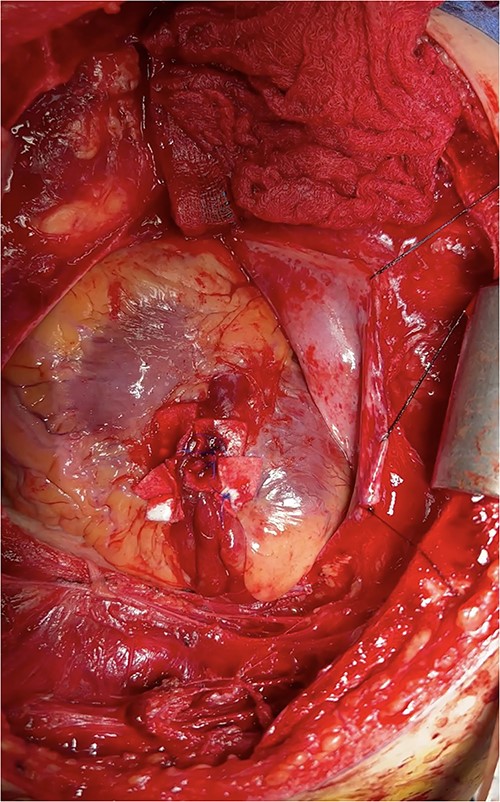

At this time, the trauma surgeons decided to take the patient emergently to the operating room. We performed a median sternotomy and discovered a 4-cm laceration of the pericardium (see Fig. 4) and left mediastinal pleura, moderate hemopericardium with thrombus, and 3-cm rupture of the right ventricle adjacent to the left anterior descending artery, consistent with the CT scan. Approximately, 2 cm of this injury was full-thickness and the remaining 1 cm was partial thickness involving most, but not the entirety, of the ventricular wall (see Supplementary Intra-Operative Video). The right ventricular injury was repaired primarily using pledgeted 3-0 prolene horizontal mattress sutures (see Fig. 5). The ventricle was hemostatic and noted to have good contractility. At this time, we performed a diagnostic laparoscopy to rule out a possible left diaphragmatic injury noted on CT. A grade I segment VII hepatic laceration was identified that was managed laparoscopically with hepatorrhaphy using electrocautery.

Intraoperative photo demonstrating pledgeted horizontal mattress repair of ventricular rupture.